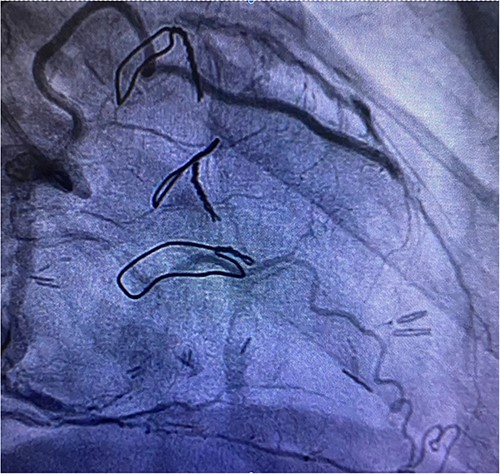

Before resternotomy, a cardiopulmonary bypass was performed via the right common femoral artery and vein. The RIMA was harvested in a semi-skeletonized fashion because skeletonized IMA is in general, longer than pedicled IMA. However, the RIMA could not reach the LAD in the present case due to cardiomegaly. Therefore, the proximal end of the RIMA was cut to use as a free graft. Subsequently, the proximal portion of the patent RA graft was tried to dissect as a proximal anastomosis site, but it was not possible due to severe adhesion of the surrounding tissue. Therefore, we decided to anastomose the proximal RIMA to the proximal right coronary artery (RCA) as the inflow site. The distal RIMA was anastomosed to the LAD as usual (Fig. 1). The postoperative course was uneventful, and the patient was discharged 11 days after the operation. A 3-month postoperative coronary angiogram showed the patency of the RA and RIMA conduits (Fig. 2). Moreover, from coronary computed tomography angiography after 6 years, it was confirmed that it was still patent (Fig. 3).

Cardiac computed tomography showing patency of RIMA to LAD 6 years after redoing CABG operation.